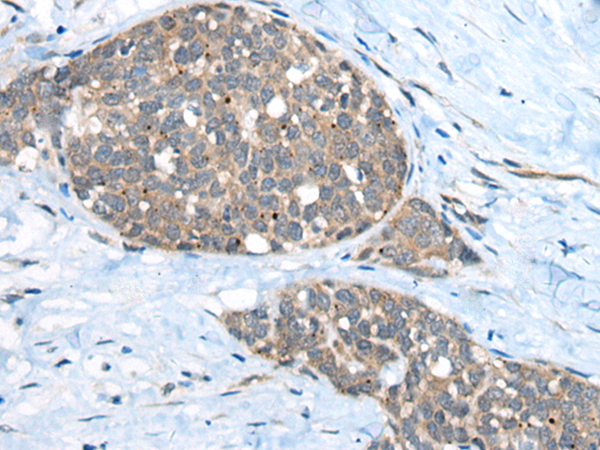

ELISA, IHC

IHC positive control:

Human liver cancer

IHC Recommend dilution:

40-200